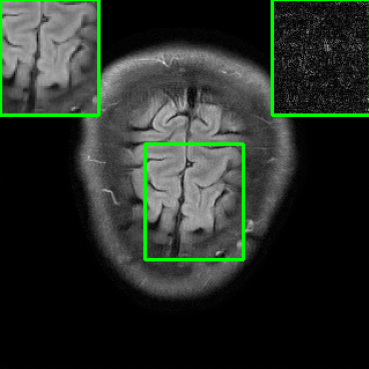

In Fig. 1-(a) and (b), we show reconstructed images using MoDL originating from a benign (i.e., undisturbed) input and a PGD-perturbed input, respectively. It is evident that the worst-case input disturbance significantly deteriorates the quality of the reconstructed image. While one focus of this work is to enhance robustness against input perturbations, Fig.1-(c) and (d) highlight two additional potential sources of instability that the reconstructor (MoDL) can encounter during testing: variations in the measurement sampling rate (resulting in “perturbations” to the sparsity of the sampling mask in ) [21], and changes in the number of unrolling steps [23]. In scenarios where the sampling mask (Fig.1-(c)) or number of unrolling steps (Fig.1-(d)) deviate from the settings used during MoDL training, we observe a significant degradation in performance compared to the original setup (Fig.1-(a)), even in the absence of additive measurement perturbations. In Section IV, we demonstrate how our method improves the reconstruction robustness in the presence of different types of perturbations, including those in Fig.1.

| Ground Truth | Vanilla MoDL | RS-E2E | SMUG |

![]() |

| PSNR = dB | PSNR = 24.84 dB | PSNR = 25.78 dB | PSNR = 30.81 dB |

| AT | Score-MRI | Deep-Equilibrium | Weighted-SMUG |

| PSNR = 30.72 dB | PSNR = 30.21 dB | PSNR = 24.58 dB | PSNR = 31.41 dB |

Results for the FastMRI Brain Dataset: we present the robustness results of the proposed approaches w.r.t. additive noise. In particular, the evaluation is conducted on the clean, noisy (with added Gaussian noise), and worst-case perturbed (using PGD for each method) measurements. Fig. 3 presents testing set PSNR and SSIM values as box plots for different smoothing architectures, along with vanilla MoDL and the other baselines using the brain dataset. The clean accuracies of Weighted SMUG and SMUG are similar to vanilla MoDL indicating a good clean accuracy vs. robustness trade-off. As indicated by the PSNR and SSIM values, we observe that weighted SMUG, on average, outperforms all other baselines in robust accuracy (the second and third set of box plots of the two rows in Fig. 3). This observation is consistent with the visualization of reconstructed images for the brain dataset in Fig. 4. We note that weighted SMUG requires longer time for training, which represents a trade-off. When comparing to AT, we observe that AT is comparable to SMUG in the case of robust (or worst-case noise) accuracy. However, the drop in clean accuracy (without perturbations) for AT is significantly larger than for SMUG. Furthermore, AT takes a much longer training time as it requires to solve an optimization problem (PGD) for every training data sample at every iteration to obtain the worst-case perturbations. Furthermore, we observe that its effectiveness is degraded for other perturbations including random noise as well as modified sampling rates shown in the next subsection. Importantly, the proposed SMUG and Weighted SMUG are not trained to be robust to any specific perturbations or instabilities, but are nevertheless effective for several scenarios.